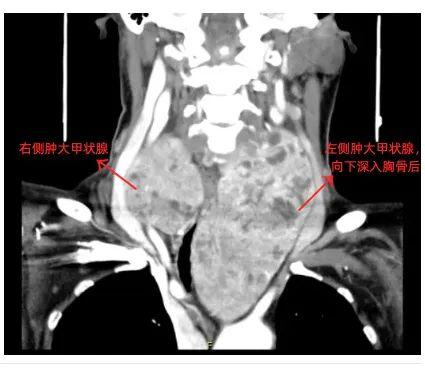

术中见双侧甲状腺腺叶非常肿大

左侧腺叶约16cm*8cm

右侧腺叶约8cm*6cm

周围血管丰富

左侧甲状腺最下缘深达主动脉弓水平下缘